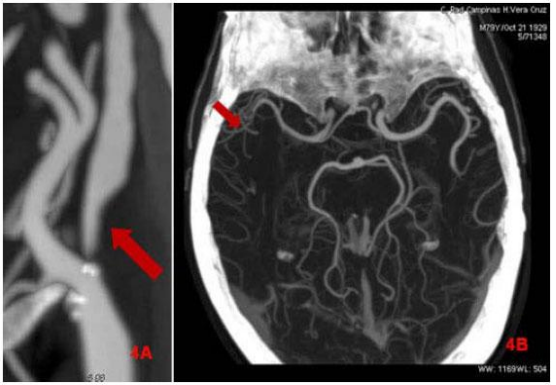

Avalie a imagem para responder à questão.

Em: